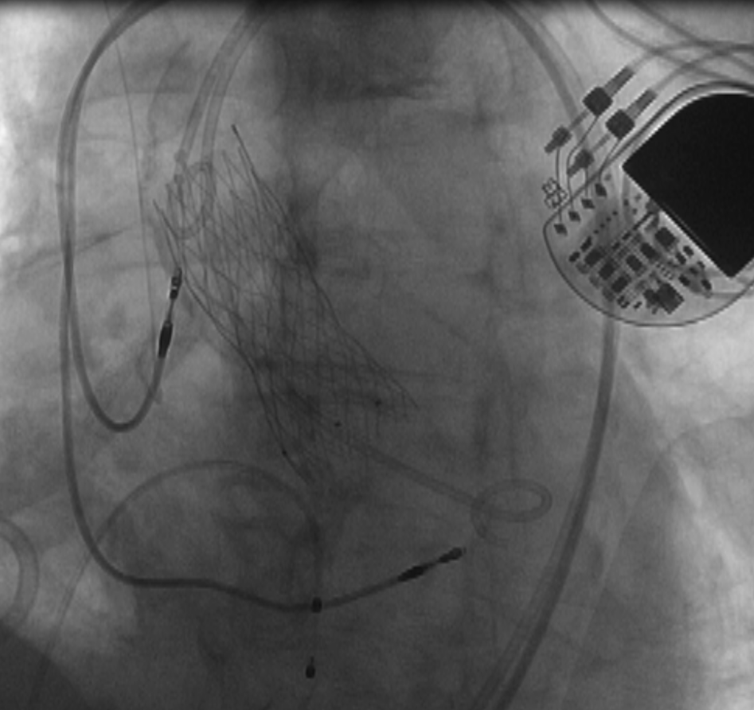

在与患者家属充分沟通并取得理解和同意后,郭延松教授带领团队联合重症医学科、麻醉科、超声科、放射科、心血管外科、手术室等多学科对手术策略及围手术期可能出现风险所制定的预案进行反复研究讨论后,决定为患者选择经皮导管主动脉瓣置入术+经皮冠脉内支架植入术,解除主动脉瓣重度狭窄,打通心脏血管的阻塞,恢复患者正常的血液循环和血流动力学,经过团队的精心操作,成功为患者修复主动脉。

经皮导管主动瓣置入术

该术式是目前治疗主动脉疾病的先进诊疗技术,无需开胸,仅需通过股动脉6mm穿刺点即可完成主动脉瓣置换,恢复瓣膜原有的正常开闭功能,极大改善患者的生活质量。我院自开展经皮导管主动脉瓣置入术以来,通过多学科团队合作已成功为众多主动脉瓣重度狭窄患者实施经皮导管主动脉瓣置入术治疗,其中80岁以上患者占比近三分之一,90岁及以上患者共5位,目前手术例数及操作水平居全国前列,为心脏瓣膜病患者带来福音。